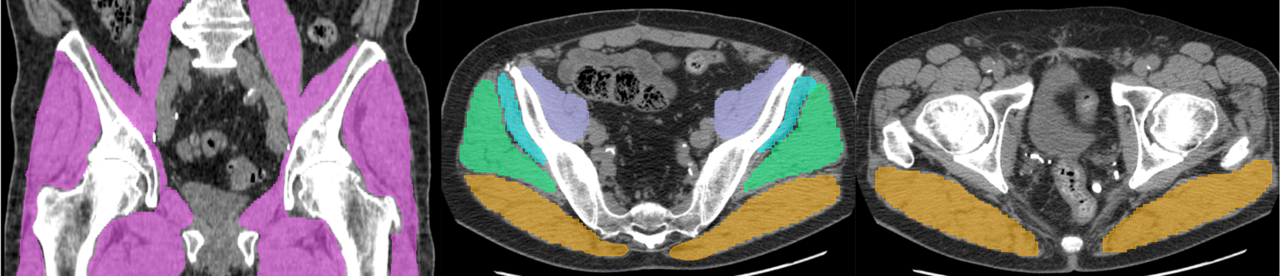

Hip Muscle

Hip muscle assessment